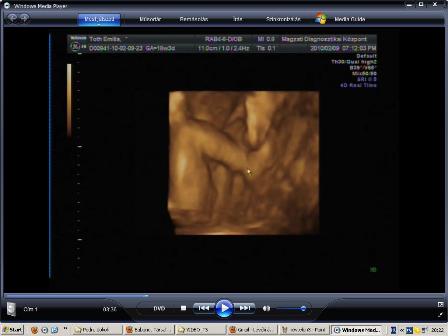

Leszedtem, a dvd-ről a fütyi+zacsi bizonyítékunkat, hogy megmutizzam :D:D:D:D

Igaz csak 2D, de jól látszik a fütyi és a zacsi is 16+6 hetesen :)

Kép